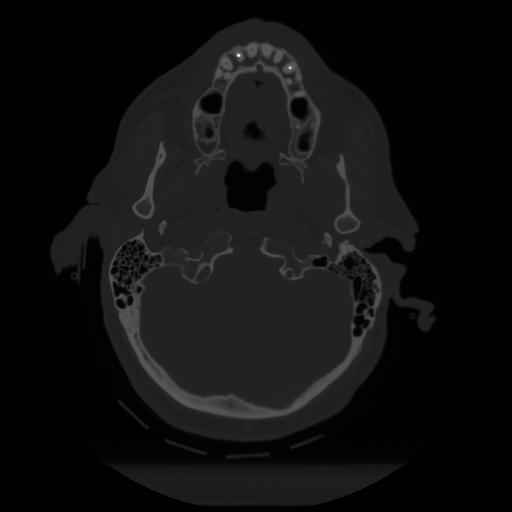

12 P.BLANDAS,,Vol,0.5,P.BLANDAS,,